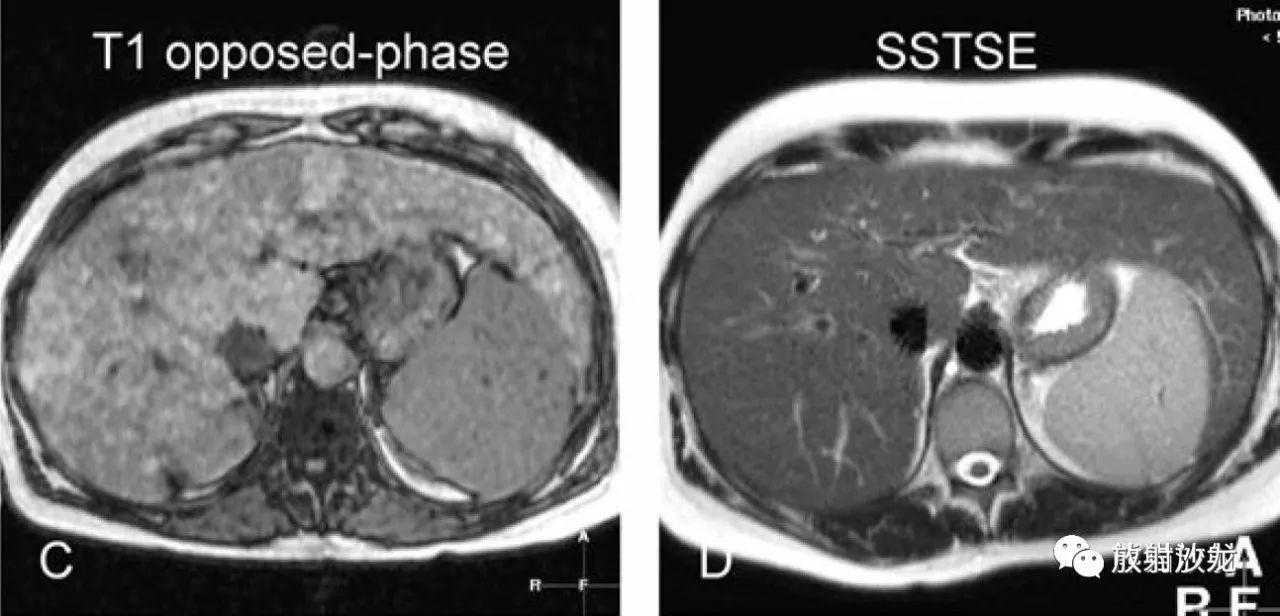

肝硬化,形态表现(来自六个不同患者):

A、C:T1WI压脂及反相位,肝内多发较高信号结节及分隔,导致肝脏形态不规则;

B、D:影像表现如上所述。